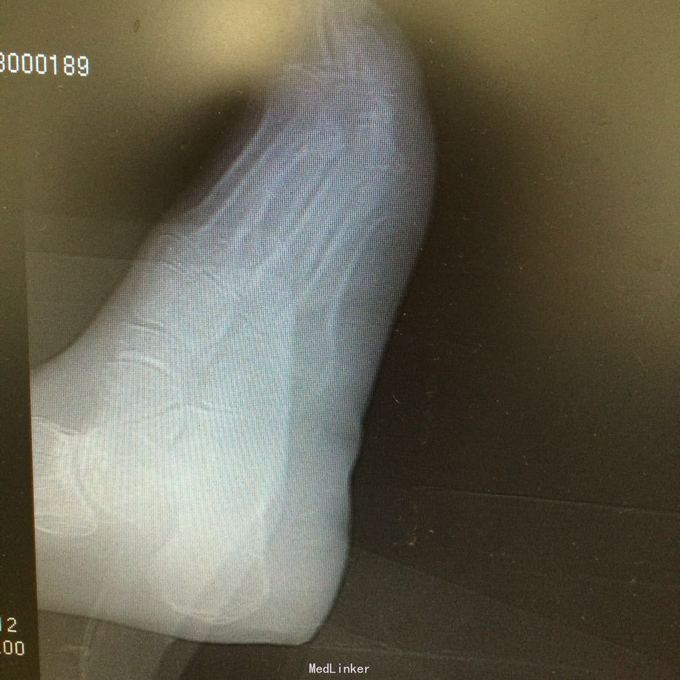

患者男,52岁。因“左跟肿痛不适二年余,加重一月”入院。 既往无特殊

左跟骨轻度肿胀,跟骨部压痛阳性,距下关节活动僵硬。左足背动脉搏动可触及,左足各趾活动、感觉正常,末梢血循环情况良好。 门诊资料:医院MRI检查(201506231473)示:“中距下关节骨质破坏,跟骨关节面死骨形成”。X线片示左跟骨上部骨质密度减低。